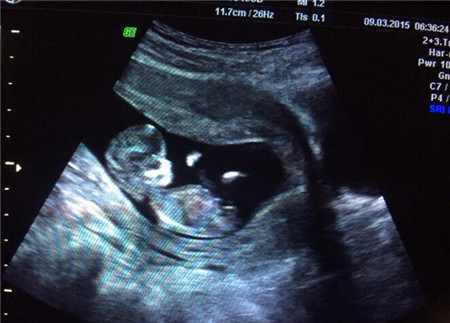

在孕早期的胚胎停止发育现象就是胎停育,如果进行B超检查,可以发现妊娠囊内胎芽或胎儿形态不整,无胎心搏动,或表现为妊娠囊枯萎。

如果通过B超检查,发现胚胎发育大于等于6周时没有妊娠囊,或都虽然有妊娠囊但变形皱缩。当妊娠囊大于或等于4cm时却看不到胎芽,胎芽的头臂长度大于或等于1.5cm却无胎心搏动,这些表现就可以判定为胚胎发育异常了。

一般胚胎8周左右有胎心,胎停育现象在8-12周就有可能出现,所以建议孕妇8周左右最适宜去做B超,以便及早检查胎儿和胎盘的发育情况,如果出现了胎心,大致可以放心。